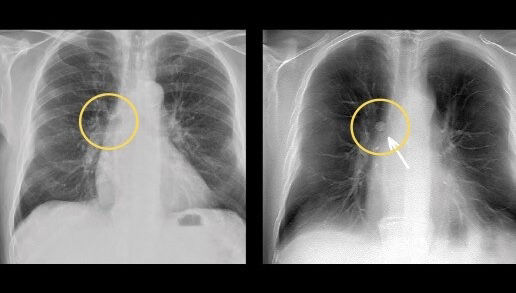

Advanced applications and IQ

Enable radiologists to consistently see more details and provide quality diagnosis